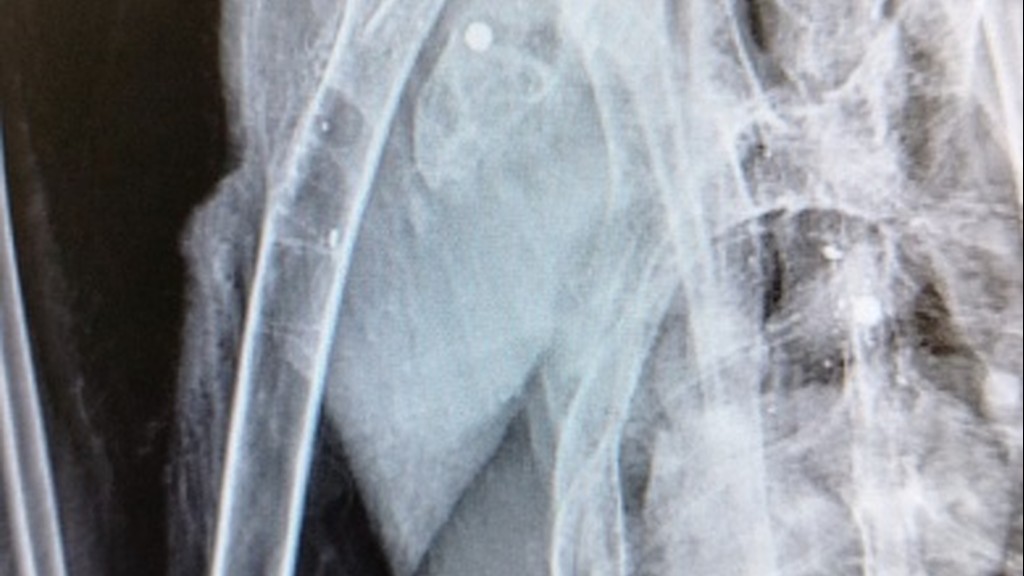

L'ibis ferito è stato trovato in un pollaio dove probabilmente cercava il suo compagno di viaggio. Due, infatti, gli esemplari avvistati in zona nei giorni scorsi. È stato un "cittadino consapevole", ieri, a portarlo al Cras Lago di Penne, che "si è subito attivato portando il giovane esemplare in uno studio veterinario specializzato che ha subito rilevato la rottura dell'omero all'altezza della cintura scapolare e ha effettuato un delicato intervento chirurgico per tentare di restituire all'ala le migliori funzioni per permettere all'Ibis di tornare a volare".

La radiografia ha confermato la "presenza di numerosi pallini da caccia nel corpo del rarissimo animale protetto". Sono stati allertati i Carabinieri forestali del Nucleo Cites, che si occuperanno delle indagini sul "folle atto di bracconaggio", cercando anche di "verificare se l'altro esemplare inseparabile Ibis, di nome 'Coccole', con l'anello numero 751, sia riuscito a sopravvivere".